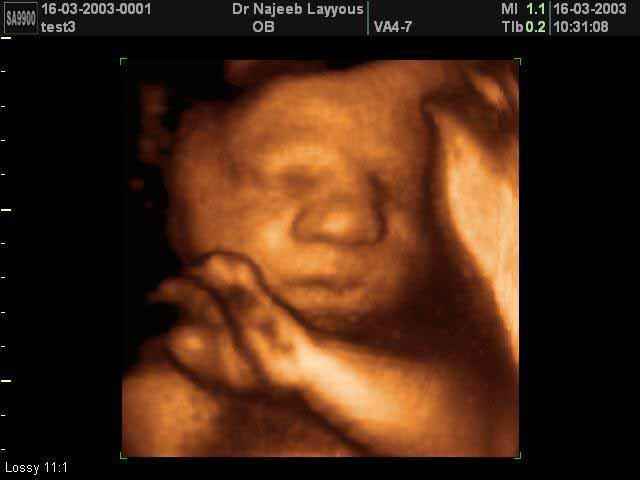

3D Fetal Face Ultrasound Scan Photos